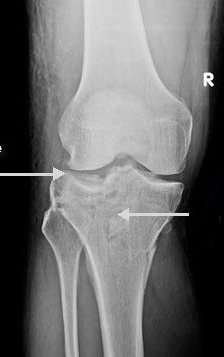

These fractures can be quite subtle and should always be considered when assessing acute knee injuries. Usually the common patterns of tibial plateau fractures are identified on plain films (AP, LAT, OBLIQUES).

This film shows a lateral tibial plateau fracture with depression and comminution. There is a less obvious extension of the fracture through the medial tibial plateau and in fact the knee is no longer connected to the shin! |